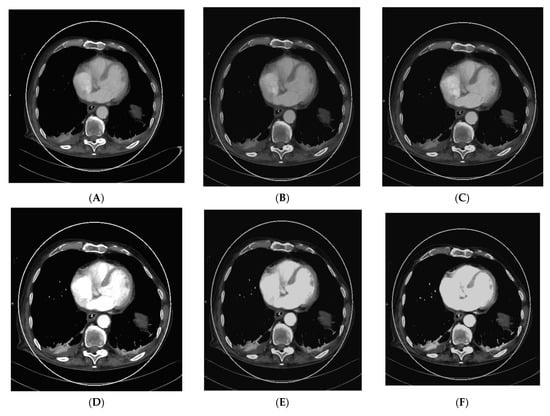

As vascular applications were one of the first fields where the benefits of DECT were demonstrated in studies and applied to routine clinical practice, aortic imaging is one of the essential fields in this context. Using DECT, it is possible to explore the effect of low-kV acquisitions using the K-edge of iodine for improved contrast in series. Martin et al. (2017), Albrecht et al. (2016), and others described that enhanced iodine contrast allows for improved detection of endoleaks; for example, in the context of thoracal or abdominal endovascular aortic repairs thoracic endovascular aortic repair (TEVAR), endovascular aneurysm repair (EVAR), fenestrated endovascular aneurysm repair (FEVAR), as well as insufficiencies and leakage of surgically implemented grafts [17,51,52,53]. Furthermore, this technique can compensate for the missed bolus and insufficient concentrations of iodine to a certain degree. The literature described that the contrast agent amount could be reduced by up to 50% in the vasculature by using 50 kV reconstructions [26]. This could be especially relevant to patients with impaired renal function, which is often associated with generalized vascular disease; however, the low-kV images also have more image noise owing to the higher rate of interaction of the photons with the atoms of the scanned body, which varies in severity depending on the DECT hardware used [6]. Figure 1 shows a case of low intravascular iodine contrast, which was caused by low-output cardiac function, as seen in the VMI reconstruction at 120 kV (Figure 1A).

Figure 1.

Acquisition of a DECT CTA of the thoracic aorta with a bad intravascular contrastation due to low output cardiac insufficiency in a 75-year-old male patient suffering from chest pain, tachycardia, and peripheral edema; (A) shows an axial view 120 kV VMI reconstruction of the descending aorta thoracalis with low intravascular contrast. Further, we see bilateral pleural effusions with adjacent partial atelectasis of the lung parenchyma. Aortic dissection could be ruled out as a cause for the clinical presentation; (B–G) show monoenergetic VMI reconstructions from 40 to 90 kV in 10 kV steps, with increasing contrast from the higher kV reconstruction of 90 kV (B) to the low-kV reconstructions with maximum intravasal contrast in the 40 kV reconstruction (G), which is closest to the K-edge of iodine, which is located at 33 kV. Accordingly, the K-edge peak is found in (G), as the highest intravasal attenuation is found here.

Consequently, VMI reconstruction was used to optimize intravascular contrast by generating monoenergetic reconstructions from 40–90 kV in 10 kV steps (Figure 1B–G, with the maximum contrast visible in the VMI 40 kV reconstruction (Figure 1G). This is especially important in the context of the visibility of small vessels, bleeding, and low-attenuation lesions. Furthermore, iodine mapping can be used to prove the accumulation of extravasal iodine in hematomas and bleeding. Using mixed images, for example, 120 kV, which is calculated from the high- and low-kV images, can improve the image noise. Furthermore, it is possible to create virtual unenhanced images or use other material-specific applications that are derived from (virtual) monoenergetic images. These monoenergetic images can be reconstructed at 40–190 kV for DSCT DECT. In this context, calcium subtraction from calcified plaques is important [17,20].